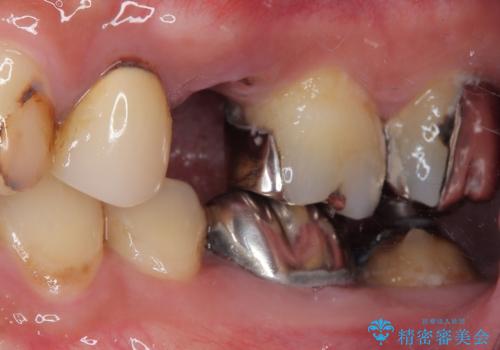

患者様の身体的・時間的負担を最小限に抑えるため、抜歯即時インプラントを選択しました。

この方法では、抜歯と同時にインプラントを埋入するため、

外科処置は1回のみ

治療期間の短縮

早期の機能・審美回復が可能

といったメリットがあります。

抜歯と同日にインプラントを埋入し、さらに仮歯まで装着するため、治療当日から見た目と噛む機能の回復が可能です。治療期間中も審美性と日常生活の快適さを維持できます。